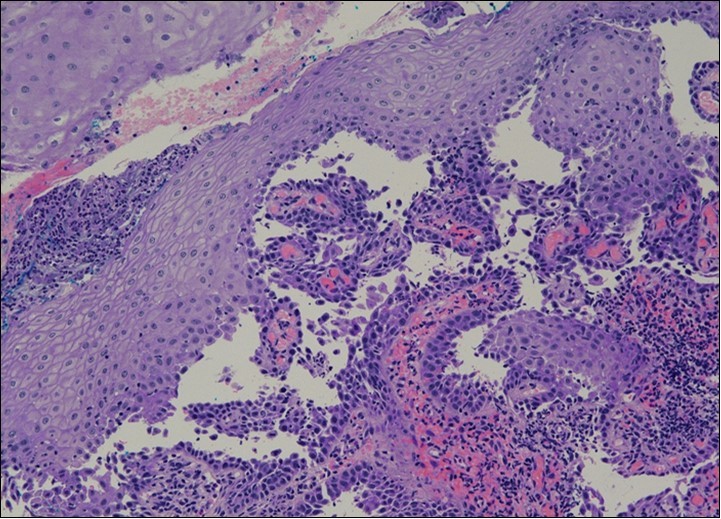

HPV test was negative for high risk subtypes of HPV. The punch biopsy specimen comprised a piece of inflamed cervical tissue in which the transformation zone was represented. The cervical tissue was covered by metaplastic and hyperplastic squamous epithelium showing intraepidermal suprabasal blister formation with acantholysis. Well vascularised dermal papillae lined residual basal cells giving rise to a tombstone appearance were present. There was no evidence of HPV, CIN, CGIN or invasive malignancy.

She was discussed at the hospital cyto-pathology conference to clarify the diagnosis. The original cytological smear specimen was reviewed, with features of bi-nucleation and koilocytosis consistent with LSIL. The cervical biopsy was also reviewed, confirming typical features suggestive of cervical pemphigus. (Figure 4a, Figure 4b, Figure 4c)

Figure 4a.Cervical tissue showing intraepidermal and supra-basal blister formation.

Figure 4b.Prominent acantholysis identified

Figure 4c.Well vascularised dermal papillae with residual basal layer giving rise to tombstone appearance